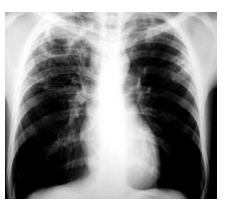

Homem de 65 anos com queixas de tosse produtiva há cerca

de 3 semanas, febre vespertina, sudorese noturna e perda

de peso. Ao exame físico, apresenta estado geral regular,

emagrecido, sem alterações na ausculta pulmonar. O RX

solicitado apresenta a imagem ao lado:

O diagnóstico provável nesse caso é